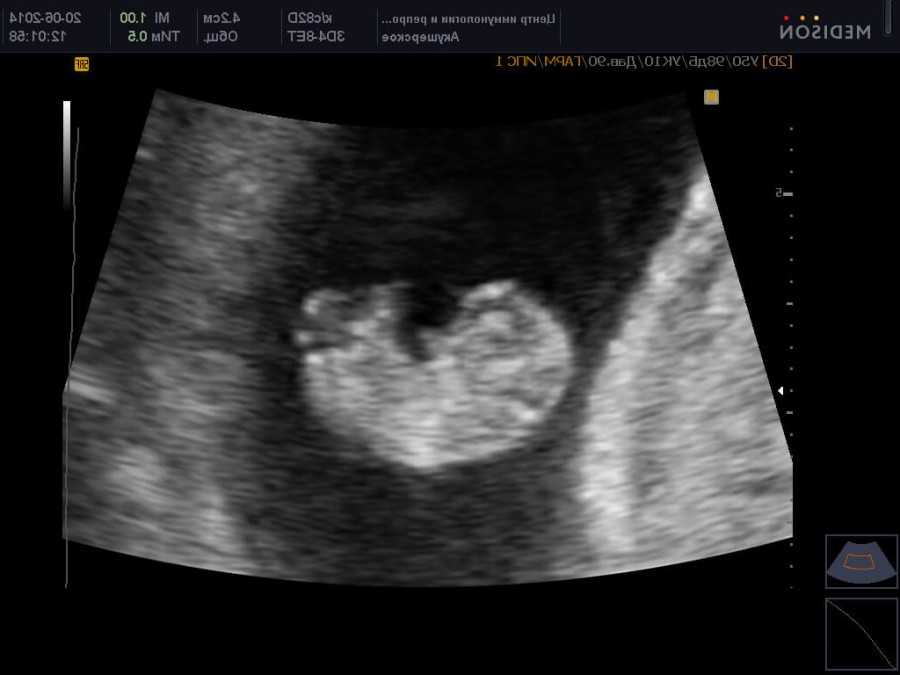

УЗИ на 9-ой неделе беременности

Ваш малыш уже официально именуется плодом, а не эмбрионом, с чем вас и поздравляем!

На УЗИ плода на 9 неделе определяется толщина плаценты и общее состояние пуповины. При помощи допплера, будущая мама может отметить частоту сердечных сокращений малыша. Хотя многие внутренние органы уже достаточно развиты, это не всегда можно увидеть на УЗИ на 9 неделе.

Внутренние органы крохи еще могут выступать в виде пупочной грыжи, но нет повода для беспокойства, ведь это совершенно нормальное явление.

На УЗИ на данном сроке обязательным является общая оценка состояния яичников.

УЗИ на сроке 9 недель